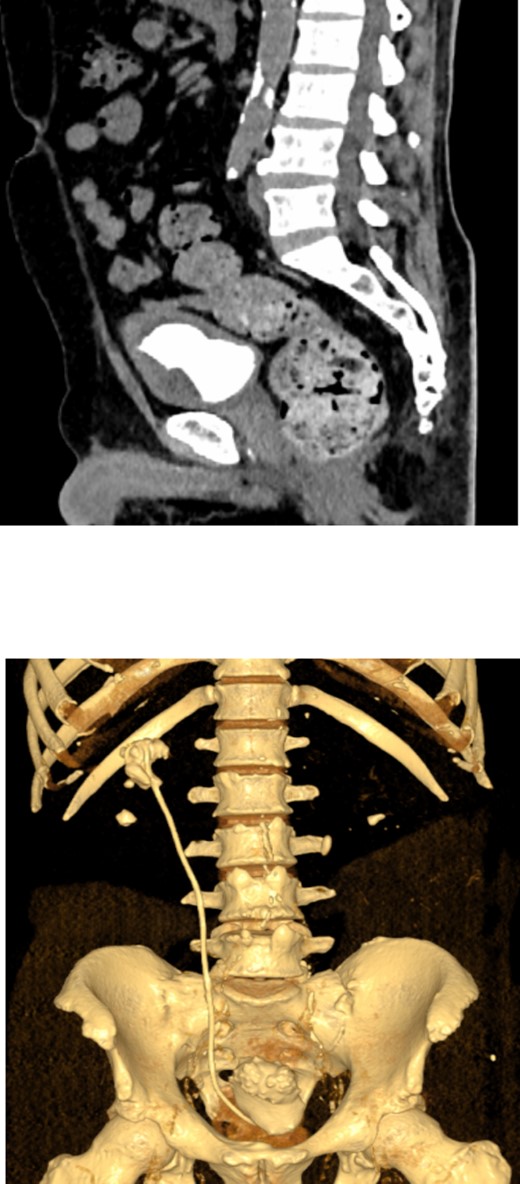

Postoperatively, a low dose non-contrast CT scan confirmed stone clearance (Fig. 6). Subsequent outpatient follow-up with renal ultrasound showed no residual hydronephrosis. The newly inserted double J stent was removed three weeks after the percutaneous nephrolithotomy procedure.

3D constructed image of postoperative low dose non-contrast CT scan showing stone clearance and newly inserted DJ stent in-situ.